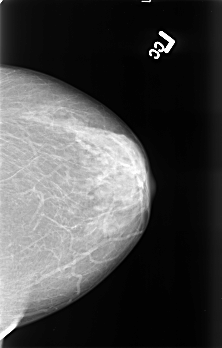

B_3395_1.RIGHT_CC

RIGHT_CC LINES 4520 PIXELS_PER_LINE 2936 BITS_PER_PIXEL 12 RESOLUTION 50 OVERLAY

FILE: B_3395_1.RIGHT_CC.OVERLAY

TOTAL_ABNORMALITIES 1

ABNORMALITY 1

LESION_TYPE MASS SHAPE IRREGULAR-ARCHITECTURAL_DISTORTION MARGINS SPICULATED

ASSESSMENT 4

SUBTLETY 2

PATHOLOGY MALIGNANT

TOTAL_OUTLINES 1

BOUNDARY